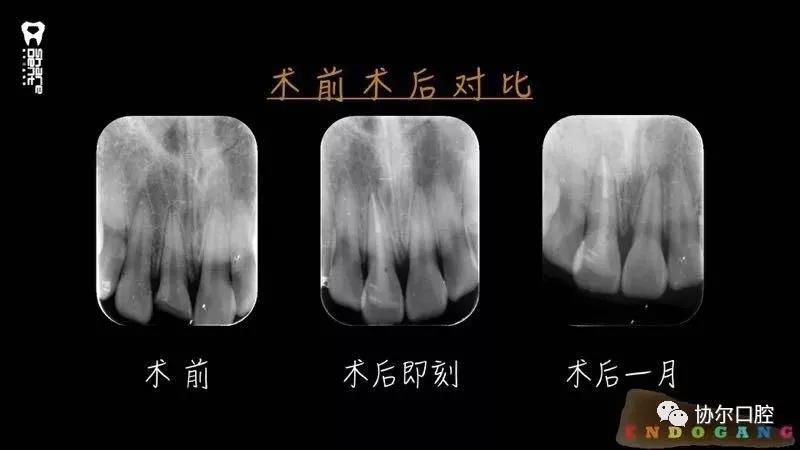

基于以上四点,使用美塑树脂进行断牙粘接是一种较好的选择和推荐。显微技术的运用进一步增加了断牙再接的精准度和精细度,为更多更长久保存天然牙以及折断的牙体组织,断牙显微再接技术值得选择和推广。